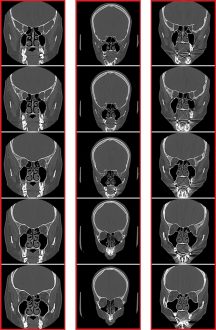

O levantamento dos dados para a pesquisa foi realizado no Hospital Estadual de Bauru, no interior de São Paulo. A base de dados utilizada era formada por 62 exames de 31 pessoas distintas. Cada pessoa dispunha de dois exames realizados em momentos diferentes, simulando o cenário ante-mortem e post-mortem. Cada exame era composto por cinco imagens dos seios frontais e cinco imagens dos seios maxilares. Ao final, o sistema apresentou 620 imagens para a realização dos experimentos.

“O que torna esta avaliação mais confiável são as estruturas dos seios paranasais, que são as cavidades ósseas. Neste estudo foi utilizado os seios frontais e os maxilares – que estão relacionadas aos tecidos duros do corpo humano, os ossos, que apresentam alta permanência, mesmo após a morte”, explica Souza Junior.